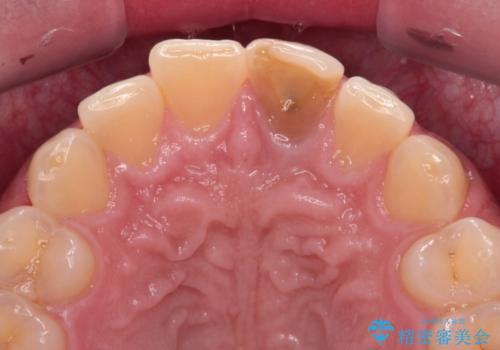

- 神経を取り除いたことで変色した前歯を気にして来院された患者様です。

根管治療はやり直さずに、ファイバーポストを使用した土台を植立してオールセラミッククラウンにて補綴することとしました。